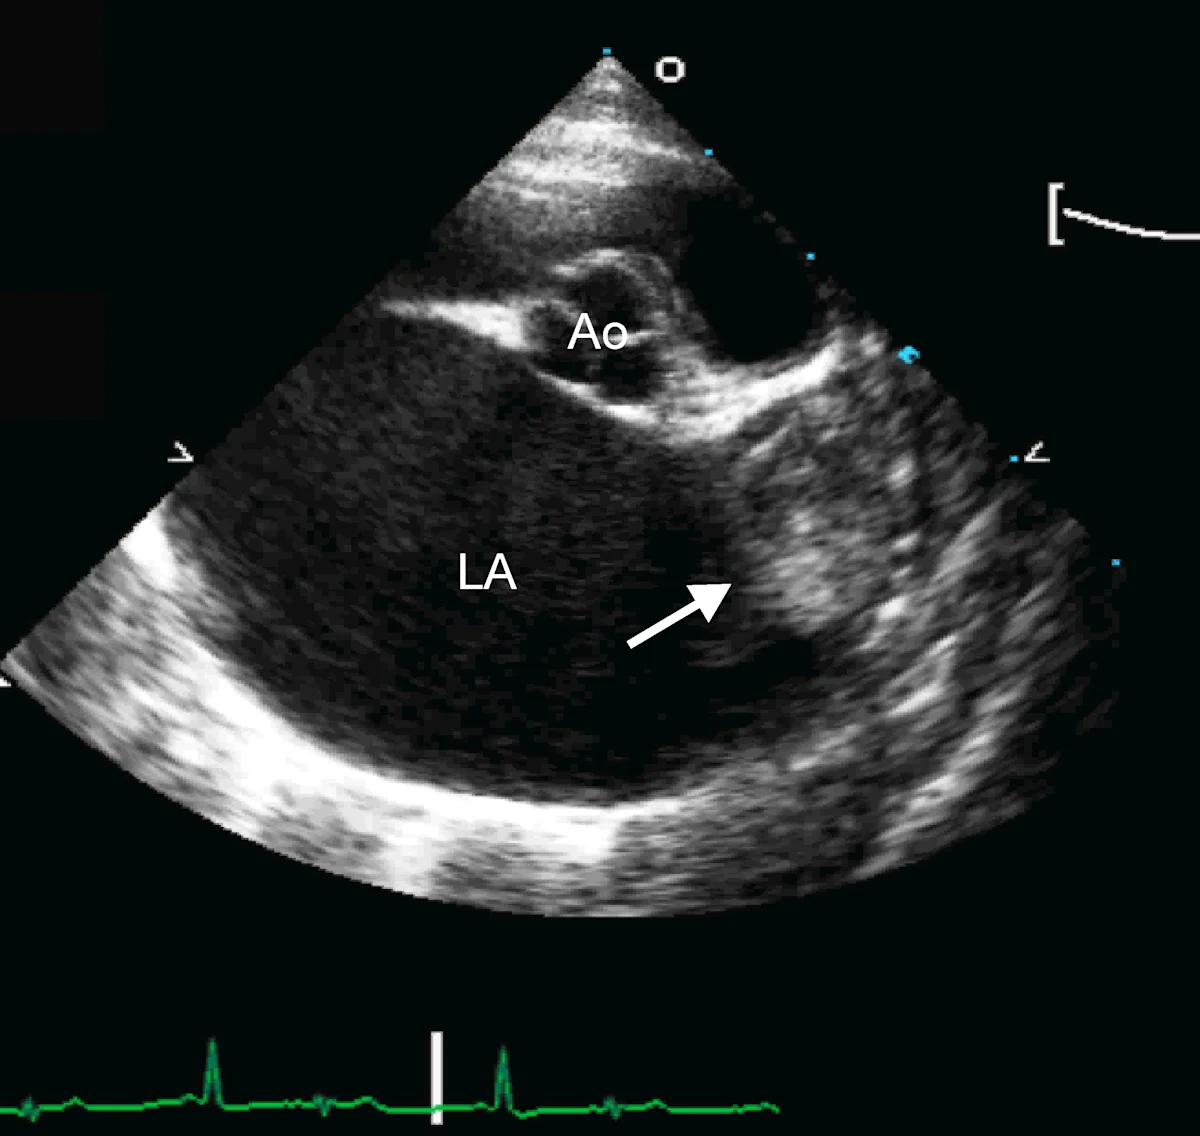

Marked left atrial enlargement was present on echocardiography after stabilization and pain management (see Treatment). A formed thrombus was apparent within the left auricle (Figure 4) and spontaneous echo contrast or smoke was present within the left atrium (Figure 5). This spontaneous echo contrast is often seen with marked chamber dilation and blood stasis; although its presence is associated with an increased risk for thrombus formation, it is not a result of a formed thrombus. Thickening of the left ventricular walls was also noted (Figure 6), which is consistent with underlying hypertrophic cardiomyopathy.

Right parasternal short-axis echocardiographic view of the heart base. The left atrium (LA) is markedly enlarged compared with the aorta (Ao). A thrombus is evident in the left auricle (arrow)

Echocardiography helped definitively diagnose underlying cardiomyopathy and the likely origin of the thrombus. The hypertrophied left ventricular wall is consistent with hypertrophic cardiomyopathy if certain conditions (eg, hyperthyroidism, hypertension) are ruled out. The markedly enlarged left atrium and spontaneous contrast indicate high risk for thromboembolic complications. In Watson, a formed thrombus within the left auricle was detected, which further supported a diagnosis of feline arterial thromboembolism.